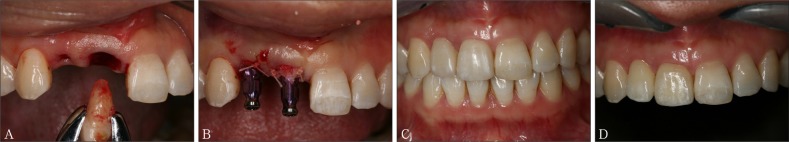

此外,当代种植系统的表面处理还有许多改良技术。Straumman推出的SLActive亲水性种植体,在氮气保护下使传统的SLA表面种植体获得更好的亲水性;Nobel Biocare的TiUnit阳极氧化技术,将传统的机械表面阳极化使其形成有骨引导作用的特殊种植体表面形态;此外还有纳米化种植体表面及种植体表面生物活性分子修饰等。种植体外形结构和表面处理对即刻种植即刻修复的意义重大,影响该项技术的临床进步与效果。北京大学口腔医院种植科自2008年4月—2011年12月共计344枚种植体行“All-on-four”即刻种植即刻修复,平均33.7个月的随访期内种植体存留率96.2%,近期效果满意[26](图3)。

图 3. 重度牙周炎患者行All-on-four即刻种植即刻修复.

Fig 3 All-on-four immediate implant placement and restoration for a patient with severe periodontitis

A:重度牙周炎患者X线检查;B:口内检查正面观;C:All-on-four即刻种植即刻修复X线检查;D:即刻修复口内正面观;E:终末修复3年后X线检查;F:唇部正面观。

图 5. 前牙美学区进行即刻种植即刻修复.

Fig 5 Immediate implant placement and restoration in maxillary anterior aesthetic zone

A:拔除患牙根;B:即刻种植并植入骨替代材料;C:临时修复3个月复查;D:终末修复3年复查。